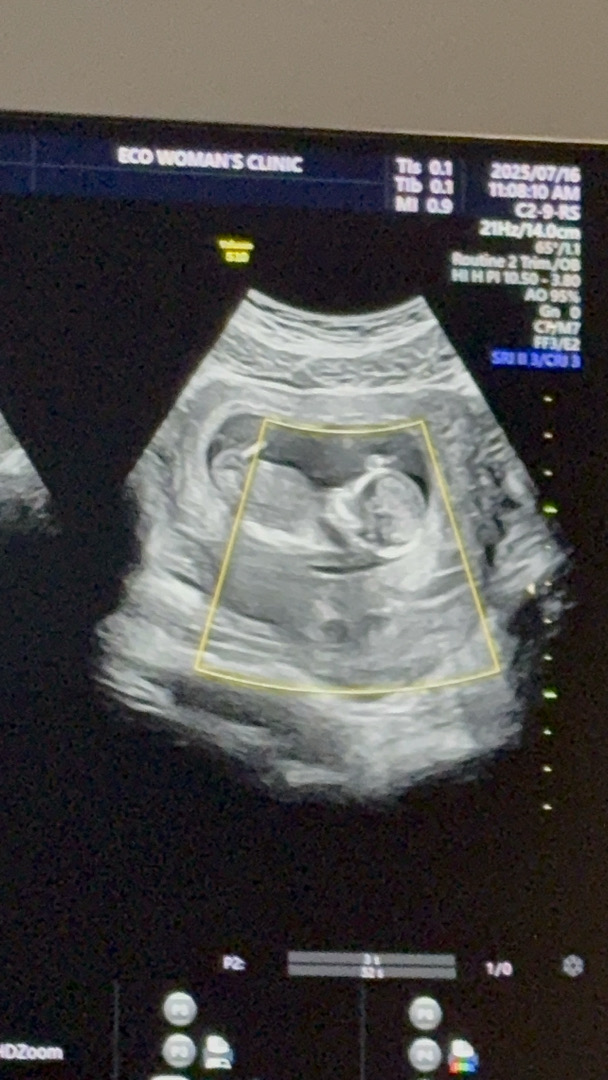

12주차 2일 각도법 슬쩍 부탁드려요 !

각도법을 적용할 수 있는 사진인지는 모르겠네요 ㅠㅠ 마구마구 의견 부탁드려요 !